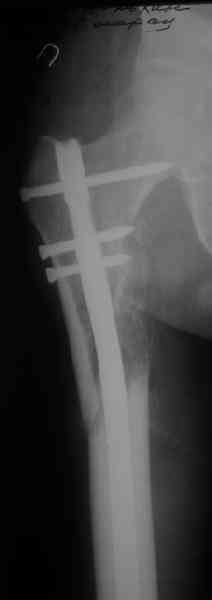

Если имеете доступ к trochanteric медуллярным штифтам TAN Smith Nephew или DePuy, где имеется offset на 8 градусов для удобства черезвертельного введения и профилактики нарушения кровеснабжения

головки (см. снимок) можно было применить штифт, в котором опороспособность достигается за счет блокирующих шурупов сверху и снизу.

На сегодня редко используются прямые piriformis штифты для антеградного введения. И универсальный Versanail от DePuy, выпускаемый для ретро-и антеградного применения с различными вариантами блокировки, в основном применяется для ретроградного введения.

Учитывая, что ложный сустав с укорочением, для восстановления необходимо применение дистракции (на кольцах или femoral distractor) или другой методикой, например после определения длины, штифт вводят в канал, не снимая Insertion tool, блокируется дистально шурупами и дальше штифт доводится до желаемого положения, затем через jig

производят блокировку проксимально

Костная масса, полученная в результате рассверливания канала, кстати, прекрасный пластический материал, можно использовать для лечения ложного сустава. Через любую трубку небольшого диаметра, без открытия фокуса, можно уложить на место дефекта. Блокирующие шурупы в 6.5 и 5.0 мм диаметра, и больной смело может передвигаться, потому что 12 мм штифт с одним дистальным и проксимальным блокирующими шурупами выдерживает вес в 75 кг.